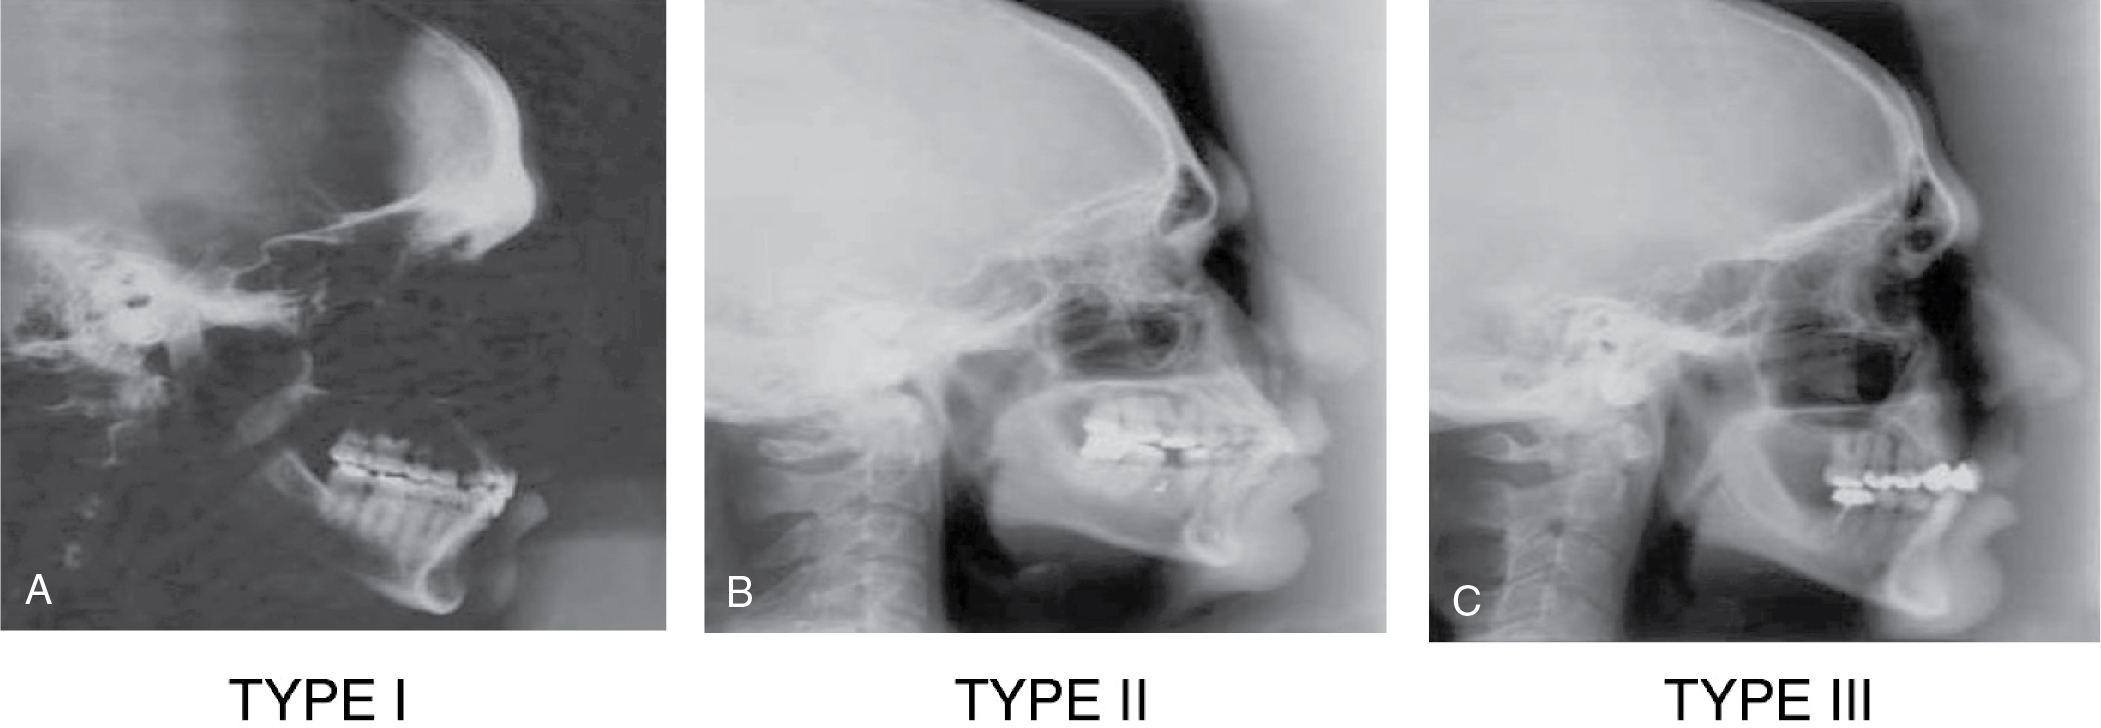

Ousterhout classification

Based on the extent of frontal sinus development, prominence of frontal bossing, and thickness of the anterior frontal sinus wall, Ousterhout described four approaches for surgical correction of bossing. Types I to III relate directly to frontal bossing and the underlying frontal sinus development and can be demonstrated with cephalograms ( Fig. 40.5 A-C), whereas Type IV relates more to forehead deformities requiring custom implant reconstructions, for which Ousterhout used methylmethacrylate, than to frontal bossing.